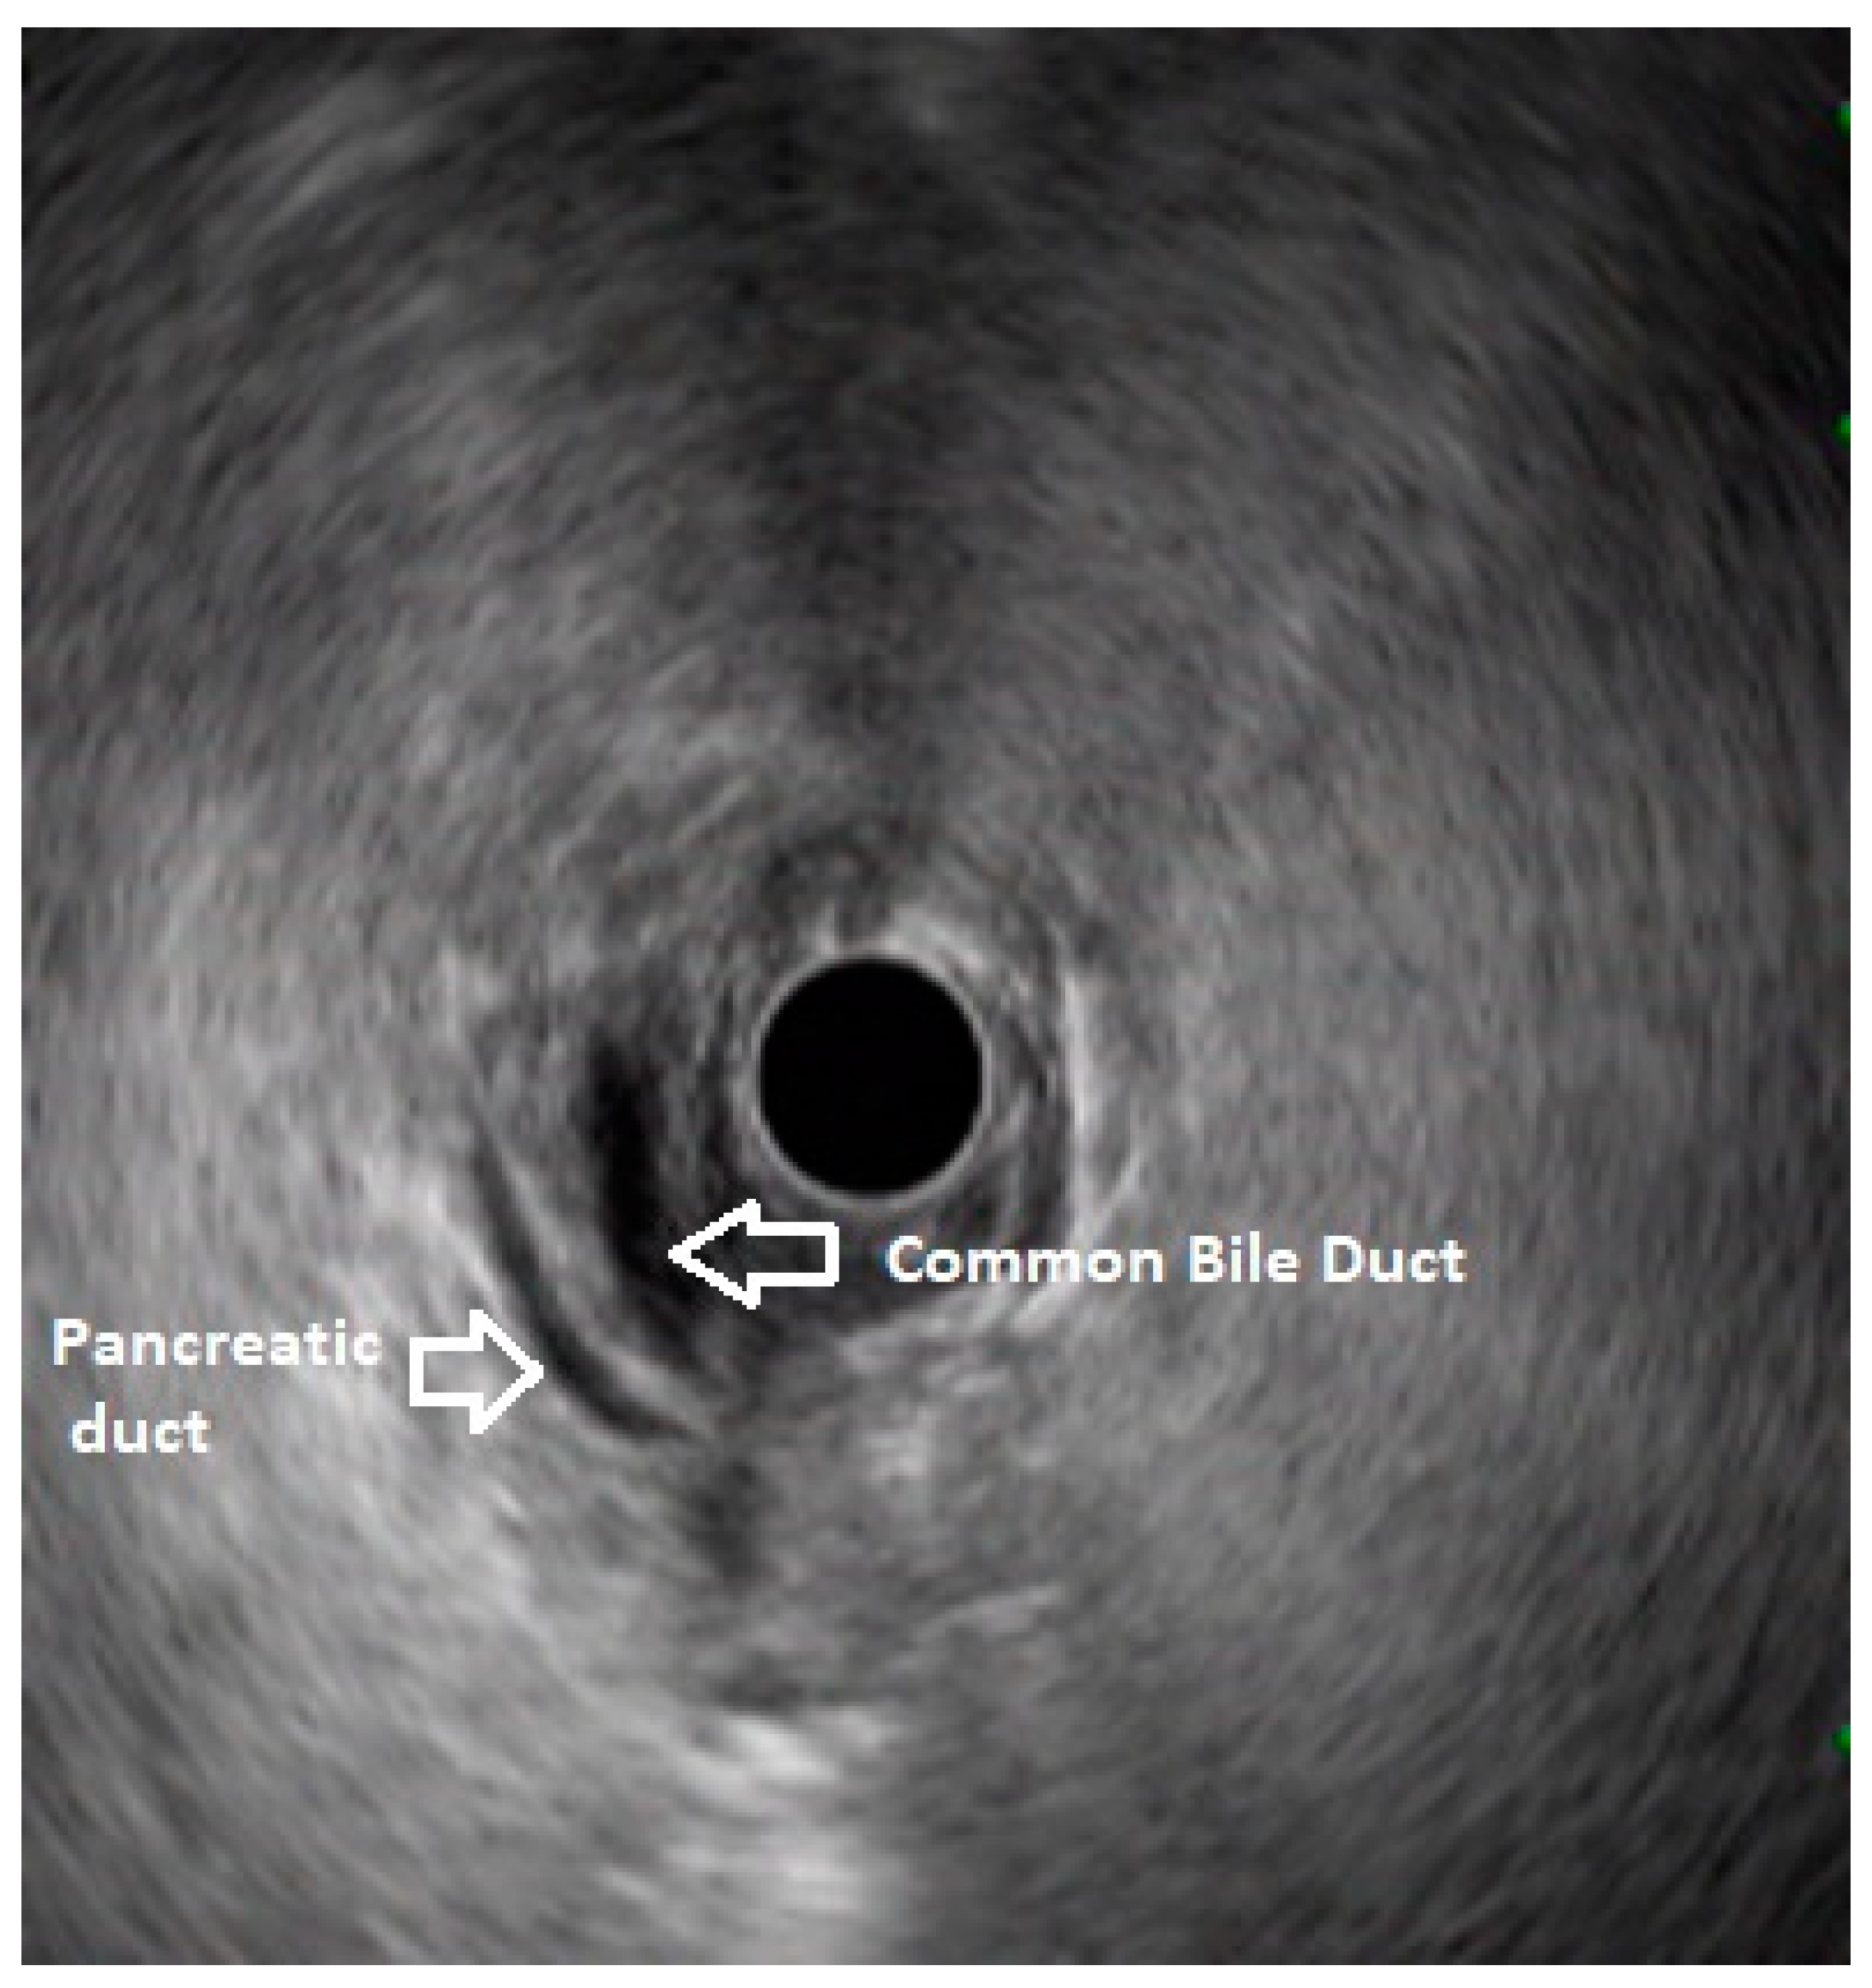

In routine endosonographic examination, all parts of the pancreas are comprehensively examined when seen from three stations, that are the apex of the duodenal bulb, papilla and distal to the papilla. Among these, the best position is the apex of the duodenal bulb as it brings the major portion of the head of pancreas, distal common bile duct and the portal vein in the same frame. For positioning, the EUS scope is advanced along the greater curvature of the stomach and when pylorus is visible, the tip of the scope is negotiated through it followed by air insufflation of the duodenal bulb. This is followed by gentle downward deflection of the tip of the scope making the duodenal bulb visible. Doppler imaging helps differentiating bile duct from the arteries (hepatic artery and the gastroduodenal artery) and portal vein. At this point, the endosonologist gets the view of distal CBD, pancreatic duct, and the portal vein in a single frame in which one structure appears to lie on top of the other and this is called as the ‘stack sign’ (Figure 1) and absence of stack sign suggests possibility of pancreas divisum (Figure 2). As these structures do not lie in the same plane, various manoeuvres like clockwise and counter clockwise rotation and right and left torque are required for a detailed examination of these structures.12 Although this sign is conventionally described in radial EUS, linear EUS can also detect similar anatomical configuration although there are some subtle differences in linear EUS. In linear EUS, usually the ‘stack’ consists of distal CBD and pancreatic duct which are seen on parallel axis (portal vein is not seen). However, superior mesenteric vein (SMV) or artery (SMA) can be seen on linear EUS in a different axis once a clockwise rotation is performed and origin of portal vein from the SMV can also be easily demonstrated (Figure 3).27

Figure 2. Radial EUS: Portal vein and common bile duct are seen but ventral pancreatic duct not seen. This finding suggests diagnosis of pancreas divisum.